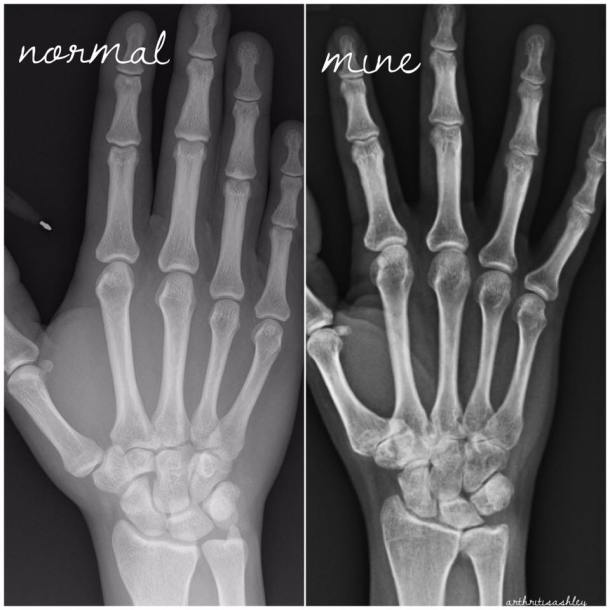

I thought I’d share these as a follow-up to my “My Joints are 90 Years Old” post.

I also need a right thumb joint replacement.

My left wrist and right foot are beyond surgical repair.

I’ve been told that my joints look 80 or 90 years old!

How can you tell? Compare joint space, shape, white areas. JIA, RA, and OA have ravaged the joints.